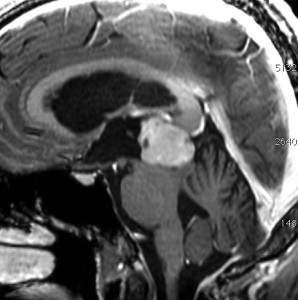

水頭症で発症した6歳児で,4cmくらいある大きな松果体芽腫でした。大学病院で第3脳室開窓術と生検術をして,脳脊髄照射30グレイ(20分割),局所60グレイ(35分割)の放射線治療が行われました。さらにシスプラチンを基剤とした化学療法が3コース行われましたが,放射線で縮小した腫瘍は少し増大してしまいました。

放射線化学療法後の画像です。腫瘍境界は不明瞭(左)で,腫瘍内出血(中央)して,左の視床に浸潤しています。かなりリスクは高いのですが,これを開頭手術で全摘出しました(右),この時点で完全寛解 CR です。この後にさらに化学療法と幹細胞移植(PBSCT,大量化学療法)が加えられました。